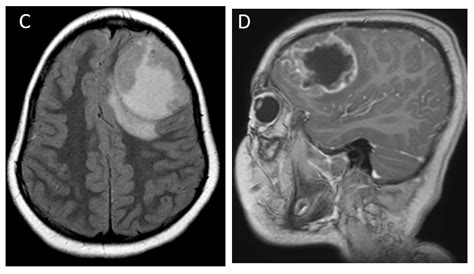

Diagnosing a brain tumor typically involves a combination of imaging tests, such as magnetic resonance imaging (MRI) and computed tomography (CT) scans. These tests help doctors determine the size, location, and type of tumor, which is crucial for planning the Brain Mass Removal procedure.

• Imaging Studies: Detailed imaging studies, such as MRI and CT scans, are reviewed to map the tumor's location and plan the surgical approach.

During the surgery, neurosurgeons use advanced imaging technologies, such as intraoperative MRI, to guide the procedure and ensure that as much of the tumor is removed as possible while minimizing damage to healthy brain tissue.